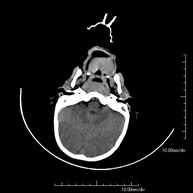

- TC Cráneo

Prueba radiológica que consiste en obtener imágenes del cráneo de alta definición anatómica (tronco cerebral, cerebelo, cerebro, calota craneal, etc.), mediante el empleo de un equipo de TC (Tomografía Computarizada).Indicaciones: traumatismos, cefalea, trastornos de la memoria, pérdida de fuerza súbita en una extremidad o mitad del cuerpo. - TC Cuello